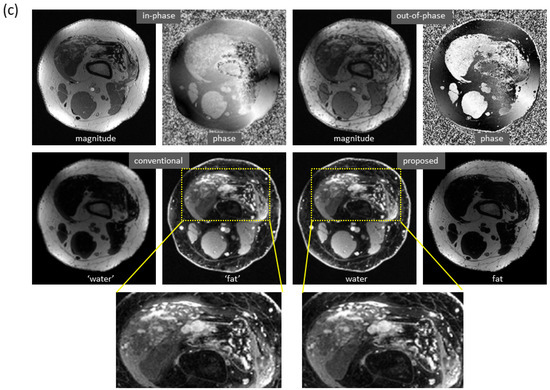

Water and fat images derived using the proposed method have high fidelity to the reference images. An example of the knee is demonstrated in Figure 3a. The differences between the predicted and reference images were negligible. In the predicted image, the enhancing tumors were well delineated. It is of note that this test set was acquired on a PET-MRI scanner (whereas the majority of the training data were obtained on MRI scanners). The models trained with only knee images also work well on out-of-distribution data from the foot, ankle, and arm. An example of the foot is demonstrated in Figure 3b (here, the images had a high spatial resolution that is not routinely obtained with dual-echo gradient echo imaging).

Figure 3. High fidelity achieved in dual-echo water–fat separation (only water images are shown). (a) Using a well-trained deep learning model, highly accurate water images of the knee were predicted from in-phase and out-of-phase images (as well as echo times, not shown in the figure). The enhancing tumors (arrows) were well delineated. Notably, this test set was acquired on a PET-MRI scanner. (b) Using a deep learning model trained with only knee images, the predicted image of the foot has achieved high fidelity to the reference image, despite inference on a different anatomic region.